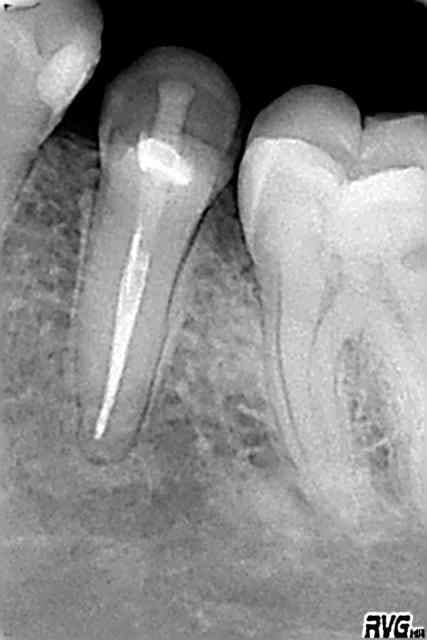

truc sympa aujourdh'ui:j'adore les casses des autres...

rassures toi inplomb avec de la patience et les instruments adequats ça sort

-instruments reprise de ttt protaper

-glyde

-limes

-racleurs

-limes sur US

-irrigation en alternance avec glyde

-petite pince très fine

-gagné

:)

cela dit je n'ai rien contre le lentulo(...) mais pouquoi celui qui casse aussi haut ne l'enlève t'il pas de suite?

pas bien compliqué ou en tout cas plus simple qd la pâte n'est pas prise

plus altruiste pr le confrère qui arrivera derrière

bref faut assumer...

zut les radios!

radios

R1 uq8spw - Eugenol

R2 hscwt1 - Eugenol

R3 bceowk - Eugenol

R4 vrw98y - Eugenol